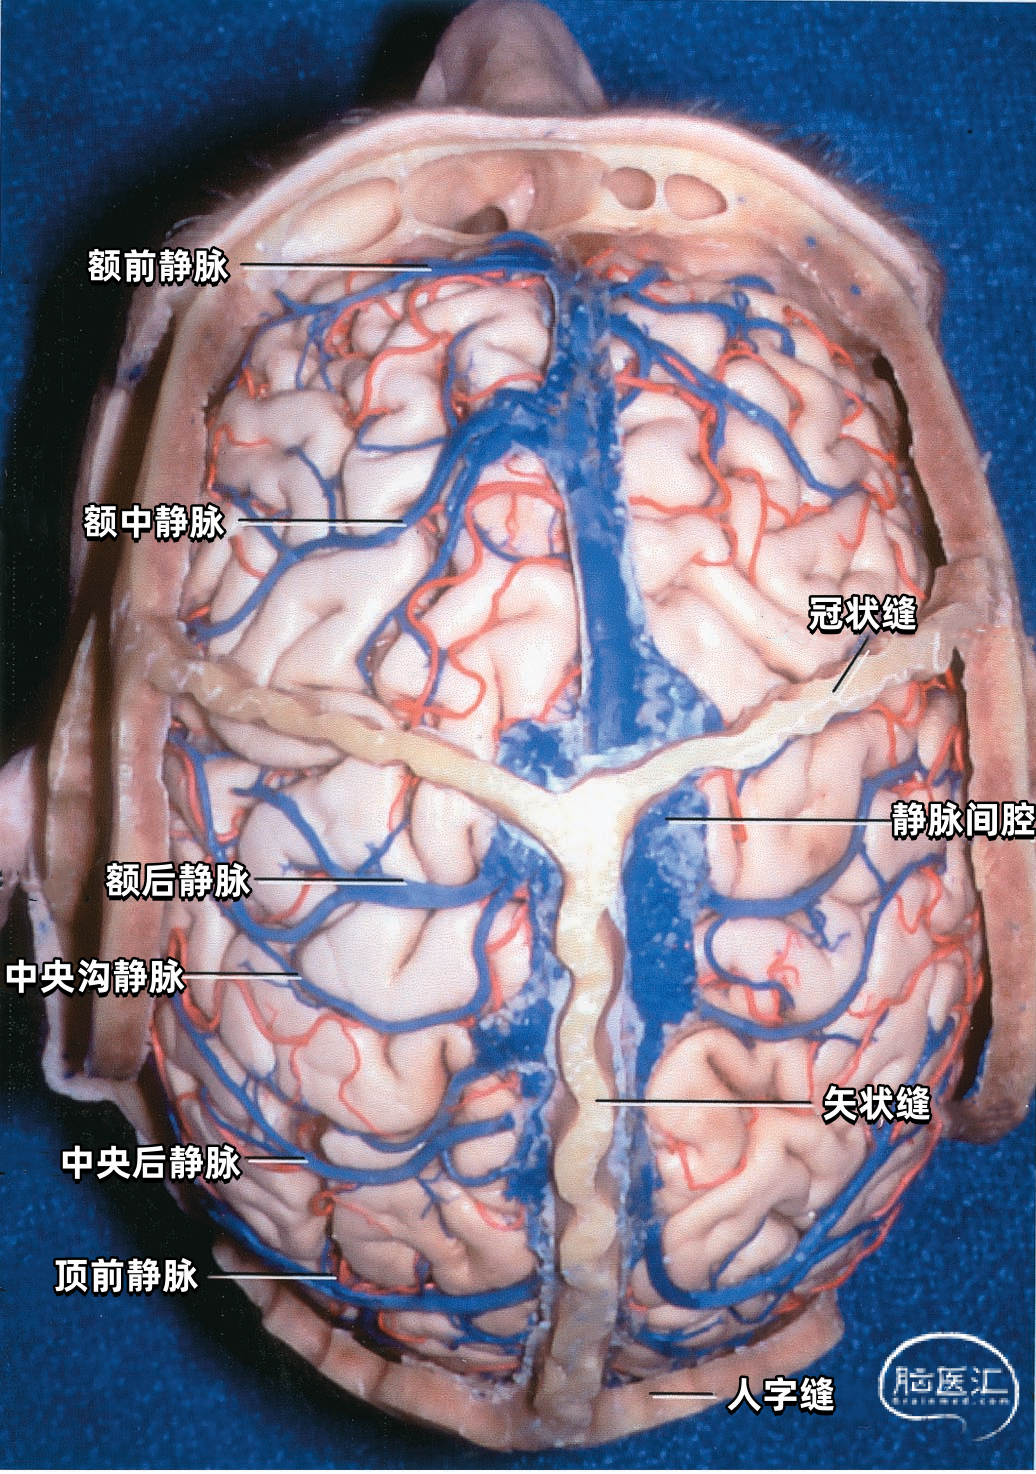

上矢状窦(superior sagittal sinus SSS)位于中线,引流额叶下面的前部和额叶、顶叶、枕叶外侧面及内侧面的上部。 上矢状窦的冠状切面呈三角形,左右两个侧角与覆盖半球凸面的硬脑膜相连接,下角与大脑镰相连。上矢状窦的三角形管腔前部较细,向后逐渐扩大。 上矢状窦两侧壁有的地方向外膨隆扩张,形成外侧陷窝。外侧陷窝常有大脑皮层静脉汇入,还有蛛网膜颗粒突入其中。上矢状窦的下角和外侧陷窝之间常有许多横行的纤维相连。在上矢状窦后部的窦壁内有一海绵状间隙系统,在窦壁内皮与硬脑膜之间,形成海绵状间隙,参与调节脑血流量。

从两侧皮层汇入上矢状窦的皮层静脉具有特有的形态(下图)。左侧显示汇入上矢状窦的静脉,右侧显示静脉入窦的平均角度。从前到后,静脉入窦的角度逐渐减小。 额极附近的静脉,与上矢状窦内血流方向一致,汇入上矢状窦; 额叶后部的静脉向前汇入上矢状窦,与窦内血流的方向相反; 顶叶和枕叶的静脉向前汇入上矢状窦,与窦内血流方向相反;| 额极静脉 110° | 额前静脉 110° |

| 额中静脉 85° | 额后静脉 65° |

| 中央前静脉 50° | 中央静脉 45° |

| 中央后静脉 40° | 顶前静脉 25° |

| 顶后静脉 15° | 枕静脉10° |

皮层静脉可直接入上矢状窦,也可经过硬膜窦引流入上矢状窦。额前部和顶后部外侧面的静脉回流倾向于加入上矢状窦旁的硬膜窦。额后部和顶部的静脉通常经静脉腔隙下面直接进入上矢状窦。 直接入窦的皮层静脉可进入窦的外侧角、外侧壁或下角,皮层静脉在入窦前可能先与窦外侧壁粘连,静脉与窦壁粘连的长度各异,最靠后的静脉最长,可达8cm。 其他皮层静脉在离矢状窦0.5~3.0cm的凸面加入硬膜窦,这些硬膜窦行向内侧进入上矢状窦外侧角。 数条皮层静脉可加入一个硬膜窦,2~3个硬膜窦可在到达上矢状窦前形成一个前庭。

下图示右侧额中静脉、额后静脉先进入靠近上矢状窦的硬膜窦。然后再进入矢状窦。额前静脉直接引流入上矢状窦。黄色箭头所指为硬膜窦,右侧有2个,左侧有3个。

下图示左侧额前、额中,额后静脉和中央前静脉不直接进入上矢状窦,而是进入额叶上缘的硬膜窦,然后进入上矢状窦。黄色箭头指示左侧的4个硬膜窦。

胼胝体膝部上方的额部上矢状窦较其他部分矢状窦接受的桥静脉少。

下图示后面观。枕叶的静脉均向前走行进入上矢状窦,因而在人字缝以下的区域(窦汇前4~6cm)几乎没有进入上矢状窦的桥静脉,这就使得手术中将枕叶抬离矢状窦而不需要牺牲任何桥静脉。

下图示右侧中央后静脉、顶前静脉,顶后静脉汇入上矢状窦。没有桥静脉汇入上矢状窦后部。抬起右侧枕叶显露小脑幕,大脑镰和直窦。在枕极和上矢状窦、直窦之间没有桥静脉。

▼2.静脉腔隙

静脉腔隙(Venous lacunae),也称为静脉湖、静脉间腔、静脉间隙,来自硬脑膜的引流静脉在上矢状窦附近扩大形成静脉腔隙,它位于两层硬脑膜之间(下图)。 静脉腔隙主要接受硬脑膜内硬脑膜静脉的回流,也引流板障静脉的血液。 静脉腔隙内壁有蛛网膜颗粒(上图),进入上矢状窦的皮层静脉(上图)往往在静脉腔隙下方走行,直接汇入矢状窦,而不是直接进入静脉腔隙。大部分途经静脉腔隙下方的静脉与静脉腔隙分别开口入窦,但有些静脉与静脉腔隙有共同的入窦开口,极少数的静脉直接引流入静脉腔隙。 也有桥静脉(上图)先在窦旁潜行进入硬膜再汇入窦,硬膜内潜行使空腔扩大形成硬膜窦。静脉腔隙和硬膜窦都与矢状窦相通。 额叶后部和顶部的静脉腔隙最大和最恒定,枕部和额叶前部的静脉腔隙较小(上图)。 通常每侧都有2或3个这样的静脉腔隙,额部一个小静脉腔隙,顶部一个大的静脉腔隙,枕部一个大小介于前两者之间的静脉腔隙。 在年龄大的个体,这些腔隙趋向于融合,以致于每侧形成一个纵长的腔隙(下图)。 下图示切除大的静脉腔隙,显露下方进入上矢状窦的静脉。左侧中央静脉在中央沟上端注入上矢状窦。右侧中央静脉向前越过中央前回加入上矢状窦。

下图示切除静脉腔隙,显示上矢状窦右侧面。可见静脉在静脉腔隙下方进入上矢状窦。额内侧静脉、额外侧静脉以及顶内侧静脉、顶外侧静脉经常在入窦前汇合成共干,然后进入上矢状窦。

下图示冠状缝前的额叶有一缺少上矢状窦引流静脉的区域,恰好适合经胼胝体入路。作者习惯用冠状缝前2/3、冠状缝后1/3的骨瓣行经胼胝体入路。

下图示侧面观(右侧半球)。冠状缝前区域没有进入上矢状窦的桥静脉。

下图示左侧一支粗大的桥静脉(黄色箭头)有额前、额中和额后静脉汇入,接受几乎所有的额叶外侧的静脉引流。在右侧,两支粗大的桥静脉(红色和白色箭头)引流额叶外侧大部分的静脉。

下图示左侧半球的前外侧面。左侧额叶前外侧面大部分由一支桥静脉(黄色)引流。在手术入路中有限的外侧暴露中,很难确定吻合静脉的情况。损伤左侧粗大的桥静脉比损伤右侧细小的桥静脉更可能产生静脉回流障碍。

上矢状窦组(上图 深蓝色)由回流至上矢状窦的静脉组成,包括引流额叶、顶叶、枕叶内侧、外侧面上部皮层以及额叶眶面前部的静脉。 注入上矢状窦的大脑外侧面静脉包括额极静脉、额前静脉,额中静脉、额后静脉,中央前静脉、中央静脉、顶前静脉、顶后静脉、枕静脉和Trolard静脉。 注入上矢状窦的大脑内侧面静脉(上图 蓝色)包括额前内侧静脉,额中内侧静脉、额后内侧静脉、旁中央沟静脉、顶前内侧静脉、顶后内侧静脉和距状后静脉。 一般静脉在离开软膜-蛛网膜注入上矢状窦前,会在硬膜下腔有1~2cm长的游离段。这些静脉可能直接汇入上矢状窦,也可能先汇入硬膜内的硬膜窦,再进入上矢状窦。

切开邻近上矢状窦的硬膜时,一定要注意保护硬膜窦,它们有可能达上矢状窦外侧2.5cm处(上图),这些窦可能接受许多皮层静脉的回流。在切除这些窦深面的上矢状窦旁肿瘤时,要沿着窦的边缘剪开脑膜,并保留与皮层静脉连接的近端和与上矢状窦的连接的远端,然后将肿瘤从硬脑膜窦的下方分离而不伤及窦。 静脉腔隙位于中央前回、中央回和中央后回上部延伸的表面,对于矢状窦旁区域的手术有可能造成很大的障碍(上图)。据报道,胎儿的静脉腔隙缺如,随着年纪增大,静脉腔隙会增大。静脉腔隙的增大会伴有进入腔隙的蛛网膜颗粒的增大。 静脉腔隙可能从大脑镰附近的大脑半球内侧扩展至半球凸面3cm的范围。由于多数静脉走行在静脉腔隙下方,独自进入上矢状窦,所以术中进入或闭塞静脉腔隙未必会造成皮层浅静脉或窦的闭塞。即使是非常大的静脉腔隙也不会与上矢状窦弥散沟通,而是通过一个小的开口与矢状窦相连,故闭塞静脉间腔通常不会影响上矢状窦的通畅性。 窦旁脑膜瘤通常起自腔隙内的蛛网膜颗粒,皮层静脉通常在腔隙的下方而不是穿过进入上矢状窦,一般不需要闭塞附近的皮层静脉。需要通过显微手术技术将这些静脉从肿瘤下缘游离出来,而不是当它们暴露在肿瘤边缘时烧闭它们。

沿大脑镰至胼胝体前部的手术入路往往需要牺牲一支进入上矢状窦的桥静脉。偶尔也可以在额前、后静脉之间达到胼胝体,而不用损伤桥静脉。这是因为经常在额前和额中静脉、或额中和额后静脉之间,有几厘米长的上矢状窦没有静脉注入(下图)。 在中央前回、中央沟或中央后回处损伤进入上矢状窦的桥静脉(下图)经常会导致对侧肢体的偏瘫,而且下肢比上肢症状明显,一般是暂时性的。这些部位的自发性静脉梗塞除导致偏瘫外,一般伴有头痛和癫痫。